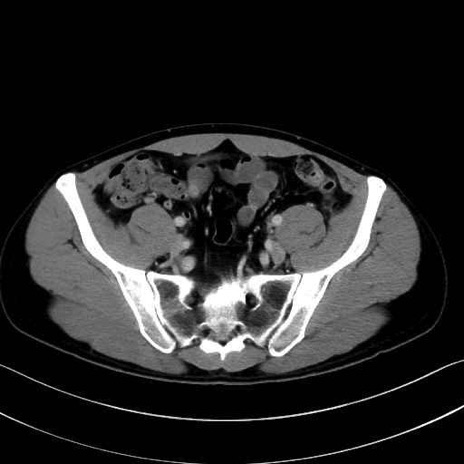

内閉鎖筋(obturator internus) のCT画像の解剖

内閉鎖筋 (Obturator internus)